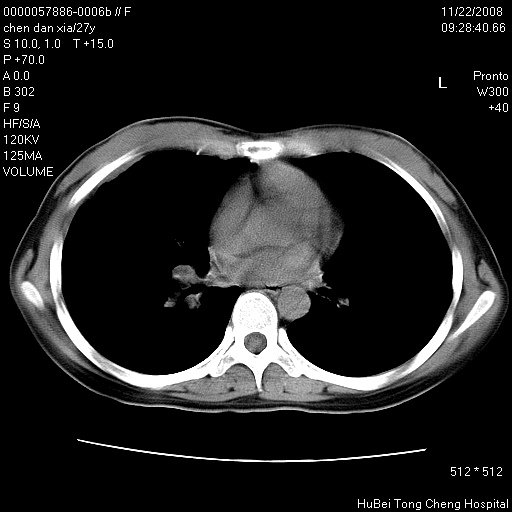

标题: CT16752:F,27Y。发热咳嗽20余天,伴盗汗。 [打印本页]

标题: CT16752:F,27Y。发热咳嗽20余天,伴盗汗。

气管前腔静脉后淋巴结肿大 右肺门纹理模糊

淋巴结核?

右下肺见片絮状影,两肺野内分布不均的小结节影,结核并肺内播散可能性大,建议结合实验室检查 .

右下肺纹理模糊;纵隔可见肿大淋巴节;右心缘旁结节,边缘光滑,纵隔窗病变范围较肺窗明显小,首先考虑右下肺结核,不排外淋巴瘤

下肺结节,结节内钙化,肺门纵隔淋巴肿大 结核可能性大